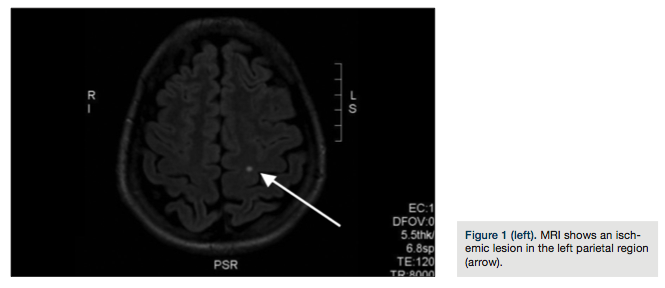

In August 2012, a 33-year-old woman was admitted to the emergency department of a local hospital due to paresthesias of the right side of the body and mental confusion. She underwent a cranial magnetic resonance (MRI) that showed an ischemic lesion in the left parietal region (Figure 1).

In order to determine the cause of her stroke, the patient was sent to the cardiology unit at INRCA Fermo. She is a non-smoker without a family history of cardiovascular disease. Her history did

not show any anomalies, with the exception of recurrent typical migraine attacks with aura. Clinical examination showed that the young woman’s general physical condition was normal; resting ECG showed no irregularities. A two-dimensional color-flow echo Doppler scan of the neck vessels showed arteries free of atherosclerotic lesions. An echo Doppler study of the lower extremities was negative for thromboses. All laboratory test tests were normal. Transthoracic two-dimensional color Doppler echocardiography demostrated a patent foramen ovale and Chiari’s network; subsequent ecocontrast with agitated saline bubble contrast demostrated a right-to-left shunt of microbubbles at rest and following the Valsalva maneuver